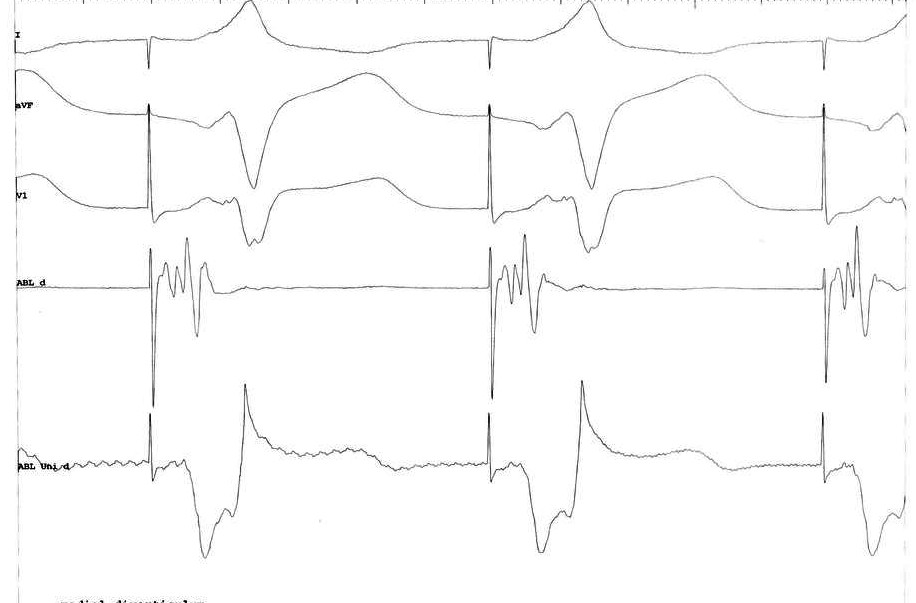

Mapping - lateral diverticulum

lateral300.jpg

Mapping - medial diverticulum

medial300.jpg

Mapping - neck

neck300.jpg

Mapping

wpw_mapping.jpg